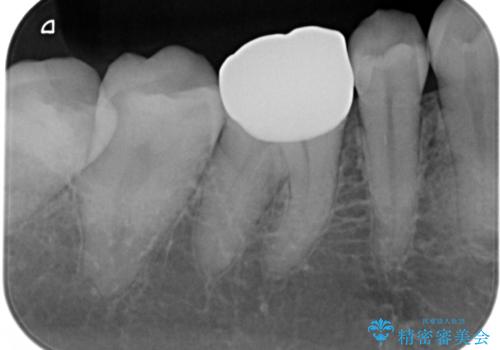

- 銀歯のやり替えをご希望された患者様です。手前の歯にもプラスチックと歯の間に虫歯が出来ていたため、両方とも適合の良いセラミックで補綴しました。

- セラミックインレー7.7万円・仮歯1.1万円・フルジルコニアクラウン7.7万円(税込)費用は治療当時の料金となります

適合不良の補綴物は二次的な虫歯発生のリスクが高まります。

自費診療で用いられる材料は保険適応の材料に比べて、より精密で適合の良い被せ物作ることができるため、長期的な虫歯のリスクを大幅に減らすことが可能です。